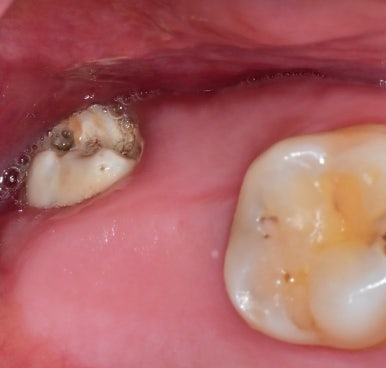

1. 옆으로 누워 난 매복 사랑니

사랑니가 옆 어금니 뿌리를 눌러

충치나 치근 흡수를 유발할 수 있습니다.

| 옆으로 누워나 발치가 필요한 사랑니 | 옆으로 누워난 사랑니를 발치하니, 앞 치아의 충치 발견 |

🔍 실제 사례: 옆으로 누운 사랑니로 인해

앞 치아에 깊은 충치가 생겨 신경치료까지 필요했던 경우가 있었습니다.